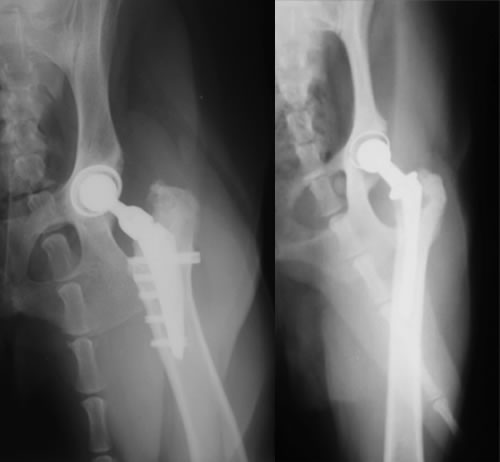

THR(Total Hip Replacement)/ 股関節全置換術

Micro THR(Micro Total Hip Replacement)/ 小型犬・猫用股関節全置換術

全股関節置換術は股関節形成不全やその他の股関節の異常(レッグペルテス、骨頭骨折等)に対して行われる根治的治療法で、機能の回復に関しては現在のところ最もすぐれた治療法です。機能しない、あるいは痛みを持つ股関節をチタンの人工関節に取り替える方法です。6カ月齢からあらゆる年齢で可能な手術です。